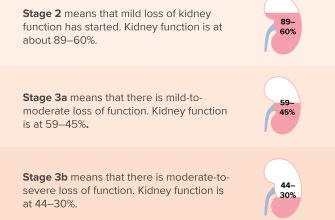

Kidney disease, also known as renal disease, is a condition

Kidney dysfunction, also known as renal dysfunction